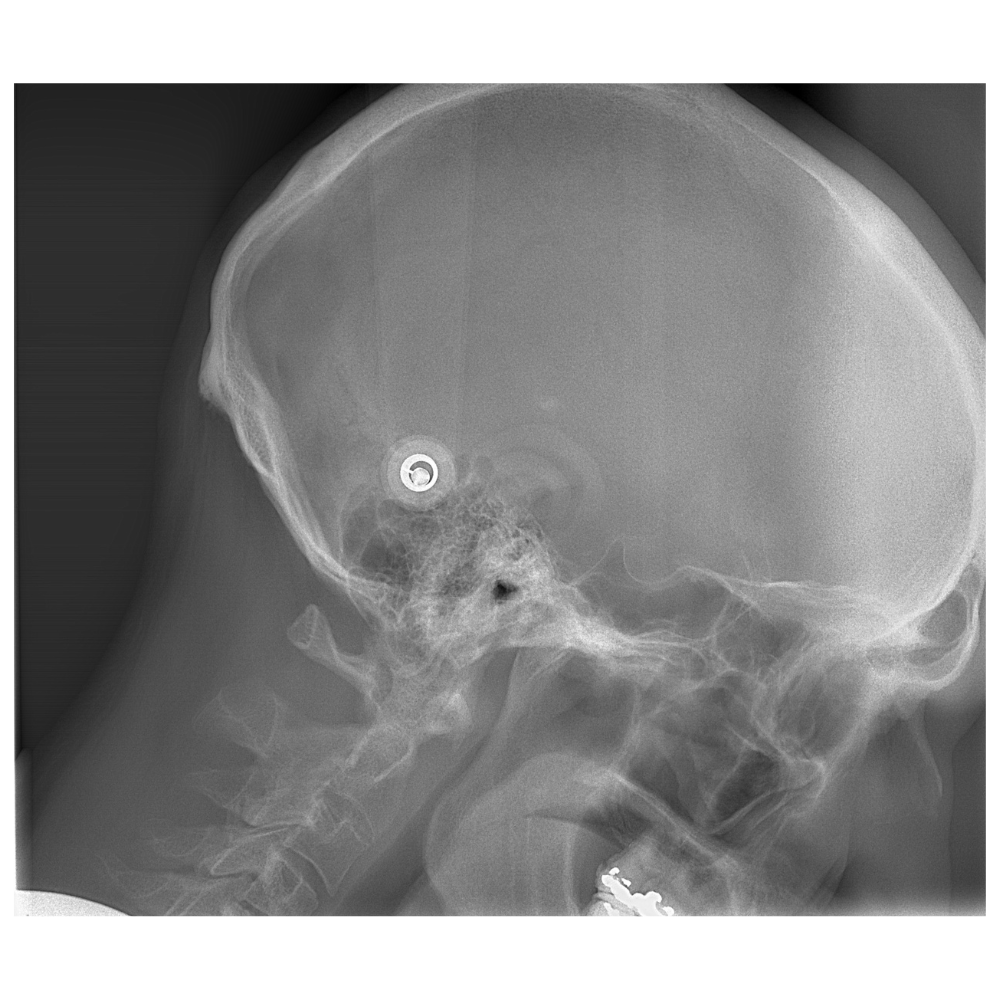

Descripción: Telerradiografía Lateral de Cráneo (Cefalometría) tomada con la cabeza del paciente en posición de flexión (inclinada ligeramente hacia adelante).

Propósito: Analiza la relación entre el cráneo, la mandíbula y, crucialmente, la columna cervical en una postura específica, buscando cómo la flexión afecta la oclusión y la ATM.